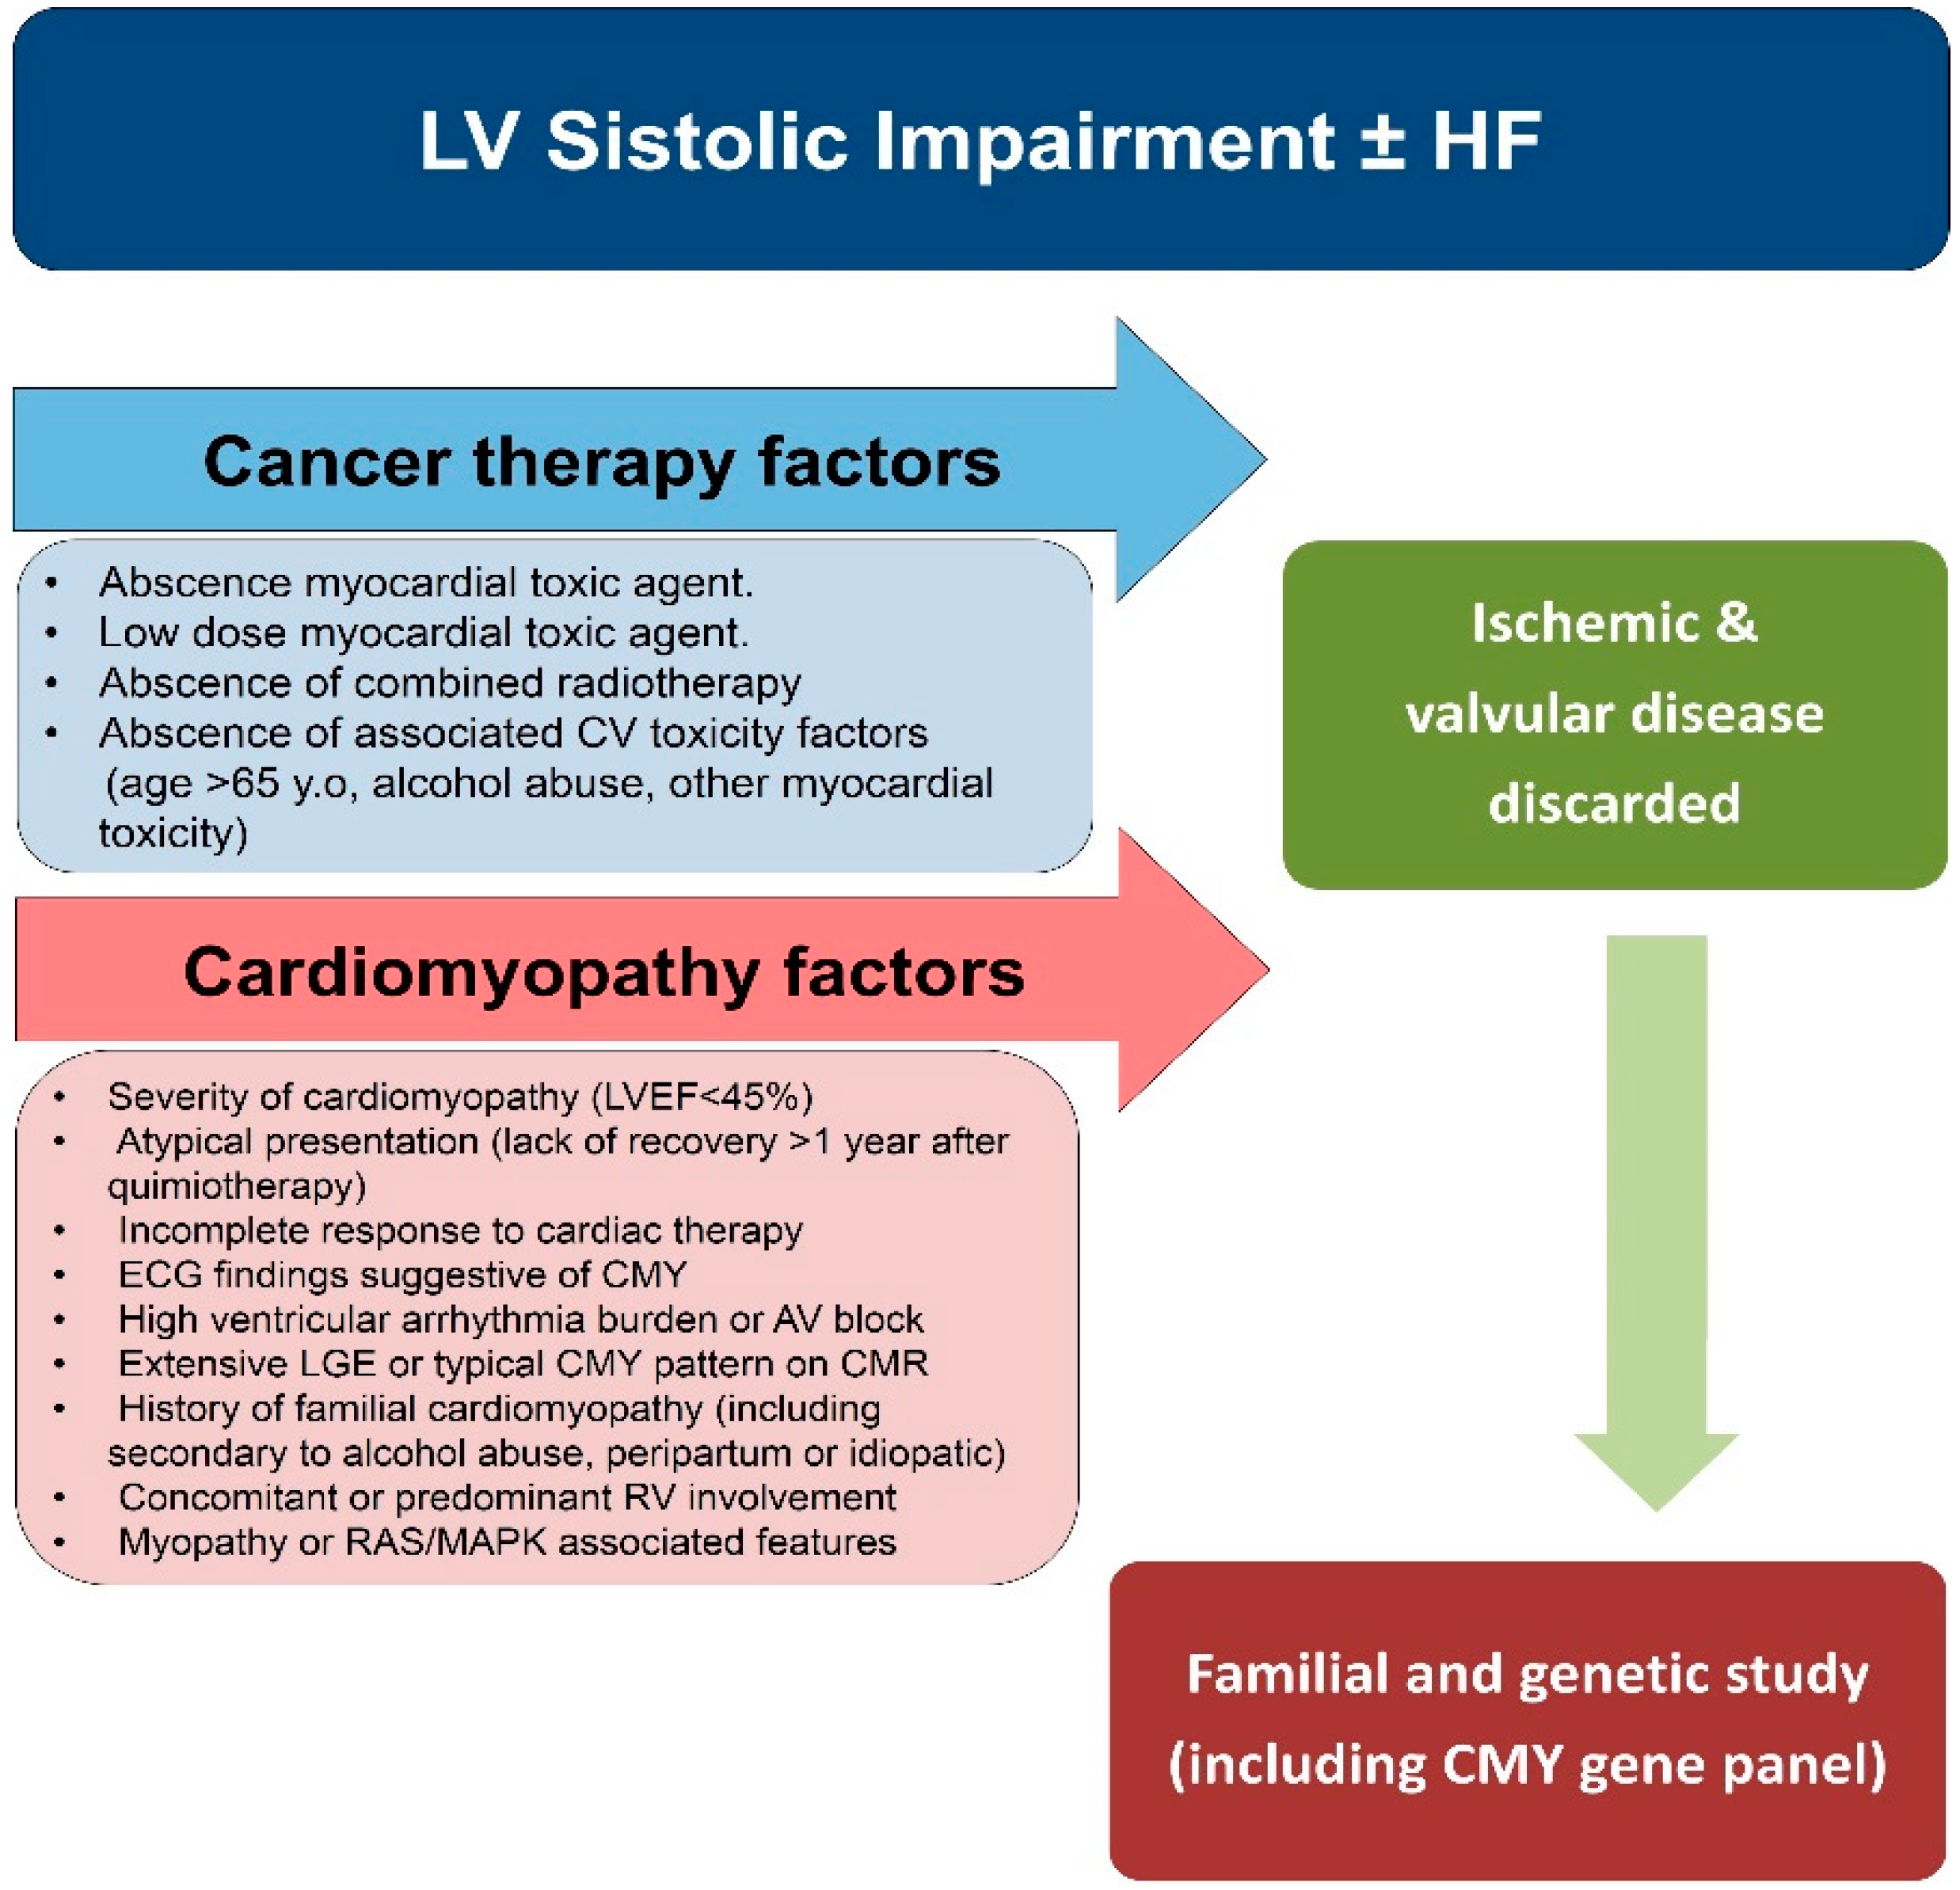

2.3. Radiotherapy

6. Importance of Genetic and Family Study in Patients with Severe Cardiotoxicity